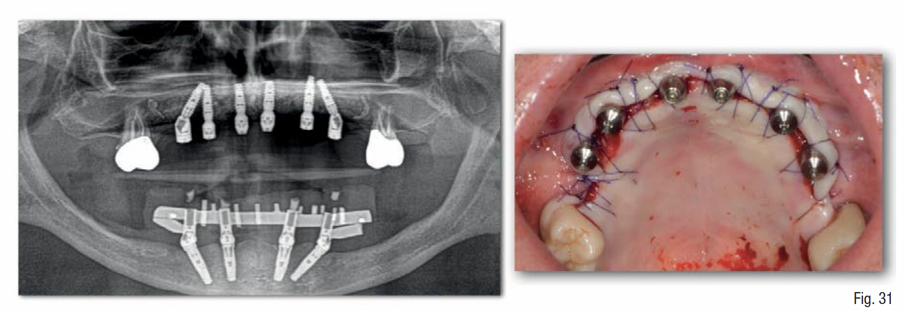

Durante la fase di chirurgia implantare, è stata inizialmente fissata la dima chirurgica sfruttando l’appoggio dento-mucoso; successivamente, è stata eseguita un’incisione lineare crestale e si è proceduto al sollevamento di un lembo vestibolare a tutto spessore e alla rimozione delle mini-viti e della griglia, che essendo osteointegrata in diversi punti è stata rimossa in diversi frammenti. La percentuale di rigenerazione, ovvero il rapporto tra il volume osseo rigenerato e il volume osseo pianificato, è stato calcolato essere del 96% (Figg. 25-29). La dima chirurgica è stata riposizionata e fissata nuovamente mediante i pin di fissaggio precedente preparati, non avendo più il supporto mucoso. Usando una tecnica di sotto-preparazione, sono stati realizzati i siti implantari e sono poi stati inseriti i 6 impianti programmati: 4 impianti dritti con dimensione 10 x 3.7 mm e 2 impianti angolati a 25° con dimensione 12 x 3.7 mm, al fine di evitare il seno mascellare (BTK implant Isy+, Biotec Srl, Dueville, Vicenza, Italy) (Fig. 30).

Dopo 4 mesi, è stata eseguita la riapertura degli impianti, verificando la loro osteointegrazione e applicando su di essi i rispettivi multi-unit abutment (MUA); inoltre, è stata eseguita una gestione del tessuto cheratinizzato mediante un lembo palatino a riposizionamento vestibolare (Fig. 31). Nei mesi successivi, sono state eseguite tutte le fasi protesiche che hanno portato alla realizzazione di una protesi fissa definitiva in zirconia e ceramica, avvitata sui 6 impianti, tipo “Toronto bridge” (Fig. 32). Il paziente è stato istruito alla corretta igiene domiciliare ed è stato inserito in un programma di mantenimento con sedute di igiene professionale ogni 6 mesi; e controlli radiografici mediante rx endorali e controlli clinici con smontaggio/rimontaggio della protesi fissa ogni 12 mesi (Fig. 33).